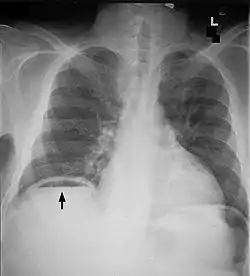

Another pneumoperitoneum on chest X-ray.